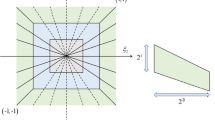

Multiple kernel scale invariant feature transform

Mathan Kumar B, PushpaLakshmi R (2018) Multiple kernel scale invariant feature transform and cross indexing for image search and retrieval. Imaging Sci J 66(2):84–97